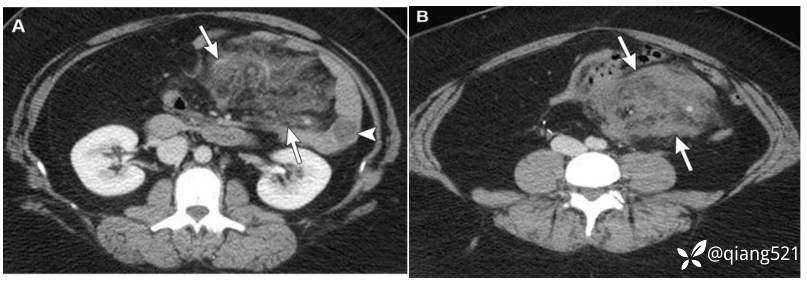

一名89岁的男性,患有转移性类癌。

横断上腹部(A)和中腹(B)的CECT显示右下象限不均匀强化的肿块(B中的箭头),右肝有一个微小的富血管病变,可能是转移性病变(A中的箭头)。患者血清5-HIAA水平升高。~(111)C-奥曲肽核素扫描显示肠系膜肿块有浓集的放射性示踪剂